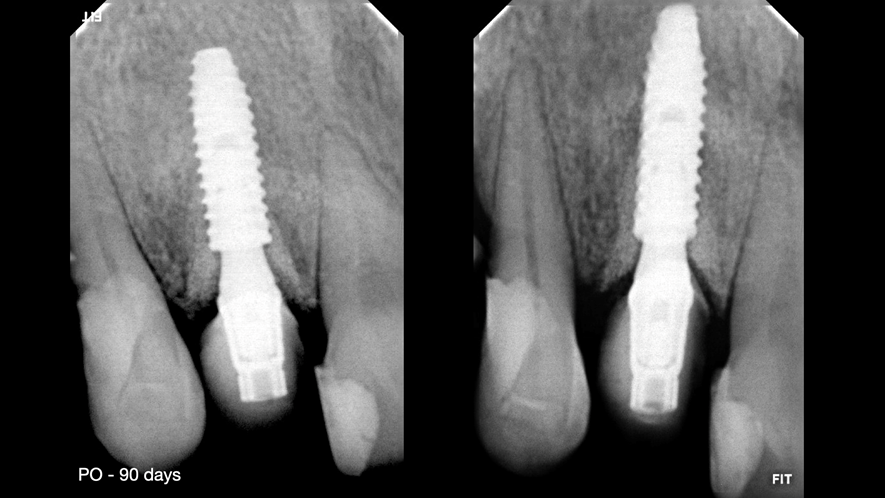

Este trabalho tem como objetivo relatar um caso clínico de exodontia minimamente invasiva de um incisivo lateral superior com fratura radicular, realizando implante imediato em alvéolo pós-extração, enxerto de tecido conjuntivo subepitelial e osso bovino liofilizado para preenchimento de GAP, prontamente à instalação de pilar reto e provisório imediato.